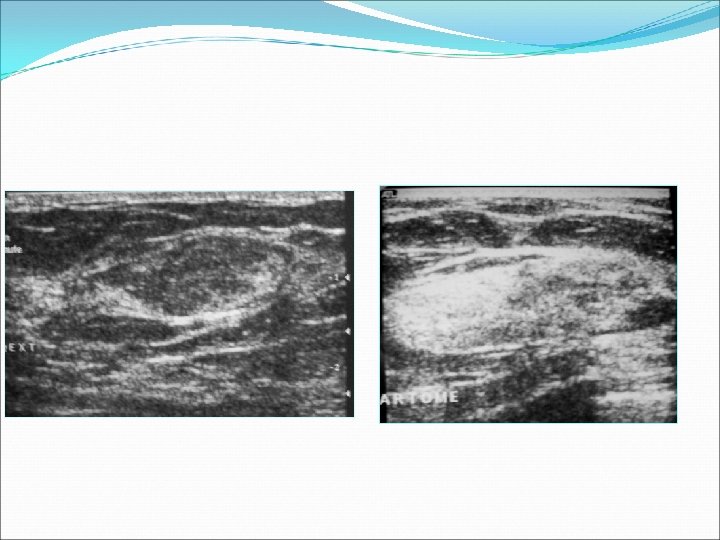

Echographie L’échographie complémentaire a montré dans tous les cas : une masse bien limitée, d’écho-structure hétérogène contenant des zones graisseuse et des zones hyperéchogène de tissu fibroglandulaires mesurant de 25 à 100 mm de grand axe.

Echographie L’hamartome présente des aspects variable en échographie. Typiquement, il s’agit d’une masse solide bien limité (66% des cas dans les différentes séries). Cette lésion est compressible sous la sonde comme la majorité des lésions mammaires bénignes. L’échostructure interne de cette masse dépend de la composition relative en graisse et en tissu fibroglandulaire. Elle est hyperéchogène hétérogène dans la majorité des cas, isoéchogène dans 30% des cas.

Echographie L’échostructure interne de cette masse est hyperéchogène hétérogène dans la majorité des cas isoéchogène dans 30% des cas et dépend de la composition relative en graisse et en tissu fibroglandulaire. Un halo entre la masse et le restant du parenchyme mammaire est visualisé dans 40 à 50 % selon les études. Et ne correspond pas à une véritable capsule mais en fait à une compression du tissu graisseux autour de la masse

Echographie La présence de microcalcifications intra tumorale est suggestive de dégénérescence maligne. L’effet sur des échos postérieurs est variable : Une absence d’effet dans 80% des cas. Un renforcement postérieur est visualisé dans 10% selon les séries. Une atténuation postérieure est considéré comme un signe de dégénérescence maligne mais peut être visualisé dans 10% des hamartome.